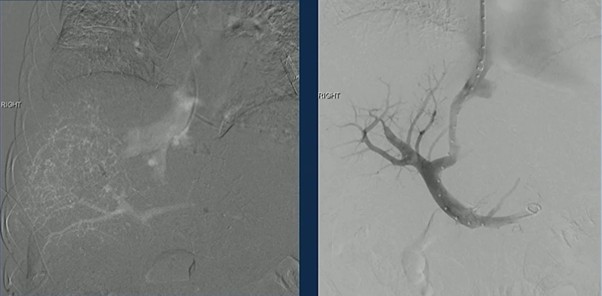

TIPS was successfully created, re-establishing outflow and decompressing the congested liver.